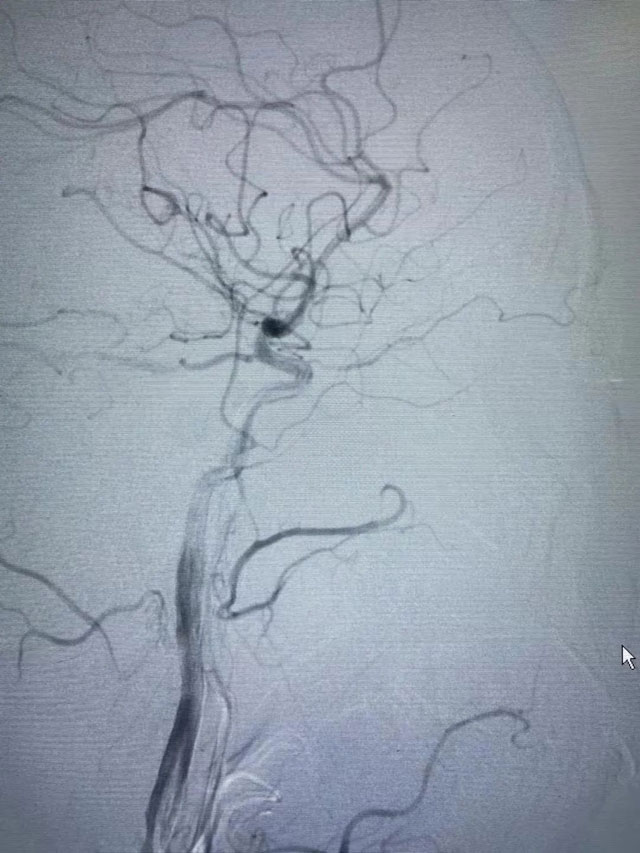

前些时候贾老先生右眼突发失明5小时,在家属陪同下,前来东方总院急诊科,1月24日晚上接到急诊会诊后,被诊断为:眼动脉栓塞导致眼动脉急性缺血引发的突发性失明,俗称“眼卒中”。黄旭东院长得知贾先生已经失明5小时了,而经皮眼动脉溶栓治疗最佳手术时间是失明后6小时以内,情况十分紧急!时间越久,失明风险越大,看着贾先生家属焦急的脸,黄院长当机立断,立即紧急启动眼动脉溶栓治疗绿色通道,为贾先生量身定制了手术方案。当天晚上,黄旭东介入团队放弃了晚上休息时间,在导管室老师们的配合帮助下,进行术前介入溶栓准备,为贾先生进行了手术。

目前,国内针对“眼卒中”主要是采取动脉顺行眼动脉介入溶栓治疗,最佳治疗时间是6小时以内,且顺行眼动脉介入溶栓经脑血管,路径长、风险大,容易造成脑出血、脑梗等问题。而贾先生的手术历时仅1个小时,就顺利完成。术后,贾先生睁开眼睛第一句话就是:“我又能看见啦!淮南东方医院介入科的专家就是厉害!”目前,贾先生视力已恢复到眼前50cm指数。